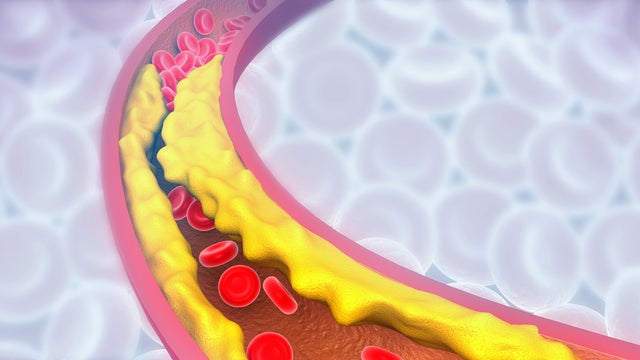

The US Food and Drug Administration on Friday approved a drug to treat high cholesterol that works differently than statins, according to Esperion Therapeutics, the company that makes the drug.